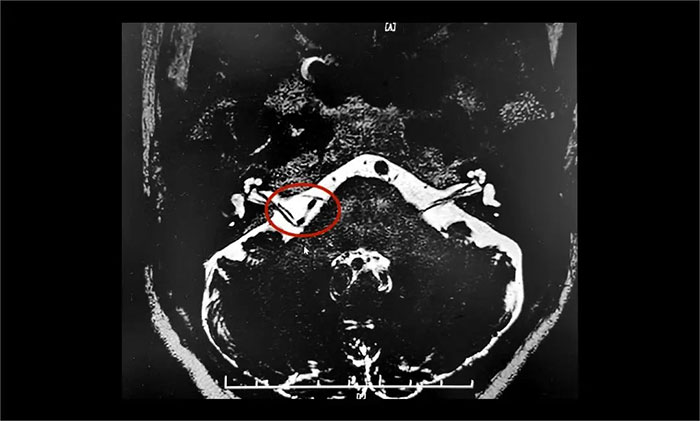

为进一步治疗,王阿姨在家人陪伴下慕名来到上海蓝十字脑科医院。入院后,杨忠旭教授团队认真评估了王阿姨面肌痉挛发生的频率、强度和持续时间,并完善了核磁颅神经检查。面神经MRTA+增强显示:右侧面神经与周围小血管关系密切。

▲ 右侧面神经与周围小血管关系密切